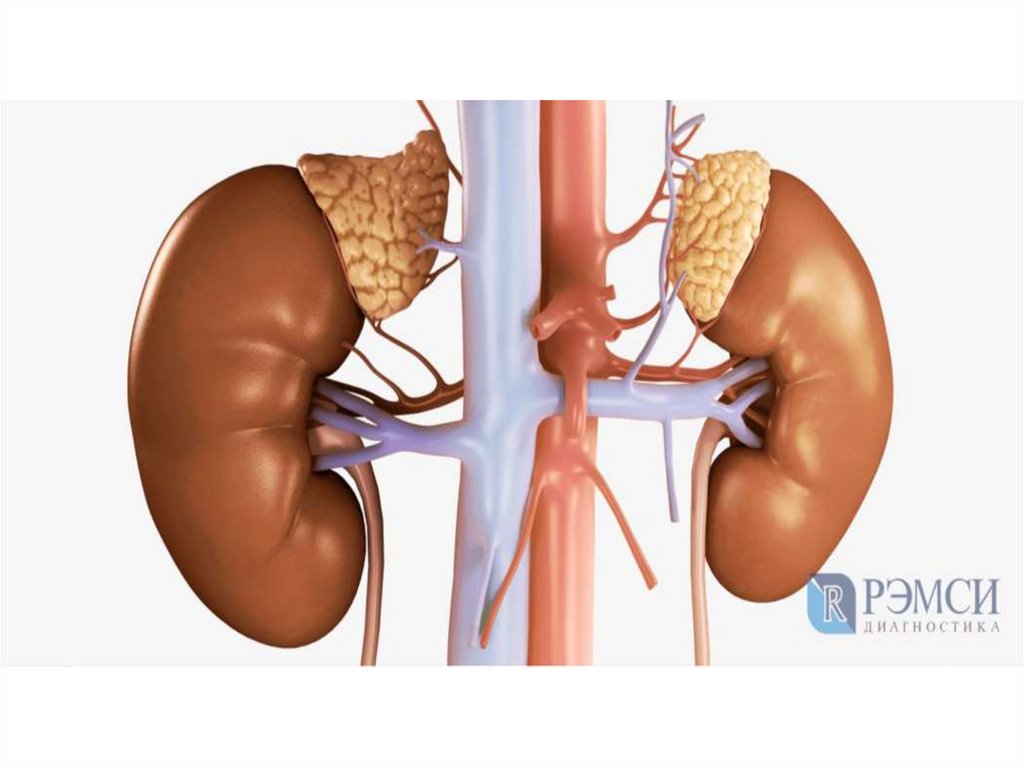

28. Артерии

• Органы малого таза питаются от общей

подвздошной артерии. Она отходит от аорты на

уровне последних поясничных позвонков и

продолжает самую крупную артерию человеческого

тела. Сначала она идет спереди от позвонков, а

затем ныряет к большой поясничной мышце.

• От общей подвздошной артерии отходят две ветви

– внутренняя и наружная. Внутренняя ветвь

короткая – всего 3-4 см. Она кровоснабжает мышцы

таза и ягодичной области, а также внутренние

органы: мочевой пузырь, прямую кишку,

влагалище.

47. Артерия круглой связки

• артерия круглой связки матки, также

известная как артерия Сэмпсона, является

ветвью нижней надчревной артерии. Она

проходит под круглой связкой матки и

питает ее. Она представляет

собой анастомоз маточной

артерии и яичниковой артерии.